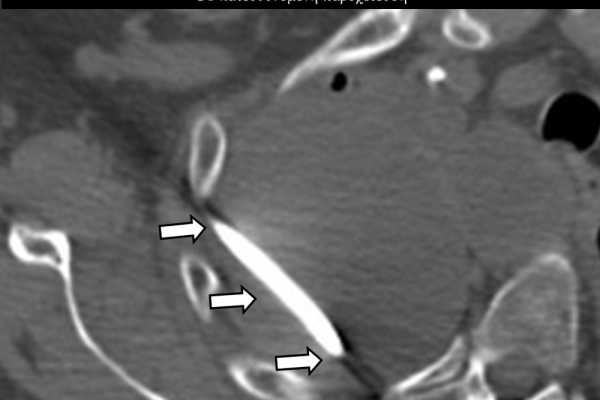

Η παρέμβαση διενεργείται υπό την καθοδήγηση αξονικού τομογράφου ή υπερήχων ή και με συνδυασμό τους. Ο επεμβατικός ακτινολόγος αρχικά αναισθητοποιεί την ανατομική περιοχή ενδιαφέροντος με τη χρήση τοπικής αναισθησίας και παρακεντεί την συλλογή διαδερμικά με λεπτή βελόνη. Στη συνέχεια μέσω ομοαξονικών συστημάτων συρμάτων-καθετήρων-διαστολέωντοποθετείται διαδερμικός καθετήρας τύπου pig-tail εντός της συλλογής, ο οποίος συνδέεται με εξωτερική παροχέτευση.